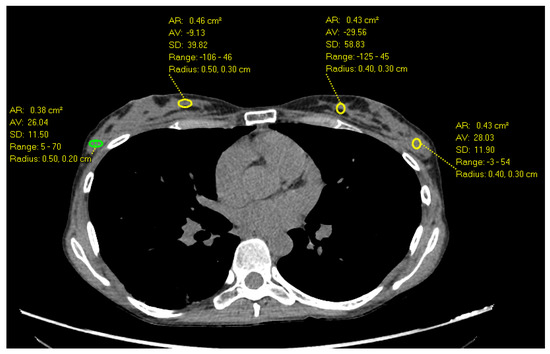

- Desperito, E.; Schwartz, L.; Capaccione, K.M.; Collins, B.T.; Jamabawalikar, S.; Peng, B.; Patrizio, R.; Salvatore, M.M. Chest CT for Breast Cancer Diagnosis. Life 2022, 12, 1699. [Google Scholar] [CrossRef] [PubMed]